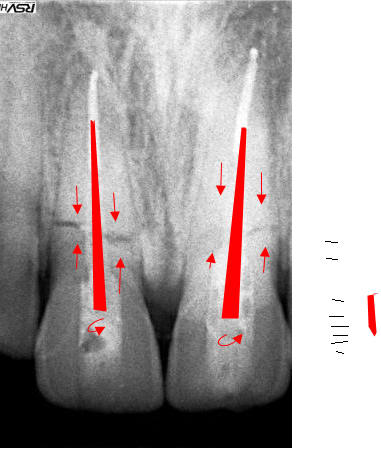

bilan 2 incisives centrales cassées net 1,5 mm sous le rebord alvéolaire

> bilan 2 incisives centrales cassées net 1,5 mm

> sous le rebord alvéolaire>

cassé trop bas pour tracter...

11 21 réduit 01 wfhbkx - Eugenol

j'ai pu à peu près réduire la fracture sur la 11 mais pour la 21 cassée en 3 pas moyen d'avoir une meilleure concordance des morceaux.

pour pouvoir maintenir les morceaux en place le temps de l'endo, j'ai coulé de la résine sur toute les faces vestibulaires de 13 a 23 en appuyant fortement sur les faces incisales, c'était assez efficace mais pas très esthétique.